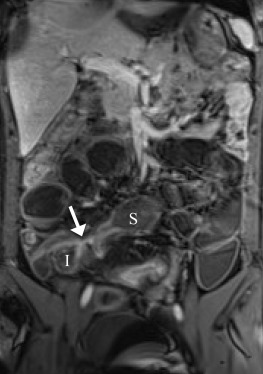

Enlarged mesenteric lymph nodes were most clearly seen on the postcontrast VIBE images, presenting as ovoid or lobulated nodular lesions between the mesenteric vessels (Figure 1 ). Engorged vasa recta were often identified adjacent to an active inflamed intestinal loop and were also best demonstrated on the postcontrast VIBE images (Figure 2 ). Fibrofatty proliferation was best seen on the coronal T2-weighted half-Fourier single-shot turbo spin-echo (T2-HASTE) images that presented as increased mesenteric fat surrounding the affected intestinal loops (Figure 3 ). Fistula tracts were often identified between an inflamed bowel and adjacent structures, showing tethering of the two structures with a contrast-enhanced fistula tract between them (Figure 4 ). Meanwhile, abscesses often manifested as fluid collections with a high signal on T2-HASTE images and well-enhanced walls on the postcontrast VIBE images (Figure 5 ).

A 40-year-old woman. Coronal T2-HASTE image shows skipped disease-involved ileal ...

Figure 3.

A 40-year-old woman. Coronal T2-HASTE image shows skipped disease-involved ileal segments with abnormal wall-thickening (arrows). There is increased amount of the adjacent mesenteric fat (arrowheads), indicating fibrofatty proliferation. T2-HASTE = T2-weighted half-Fourier single-shot turbo spin-echo.

A 25-year-old man. Coronal postcontrast VIBE image shows affected tethering ...

Figure 4.

A 25-year-old man. Coronal postcontrast VIBE image shows affected tethering segments of ileum (I) and sigmoid colon (S), with an enhancing fistula tract (arrow) between them. VIBE = volumetric interpolated breath-hold examination.